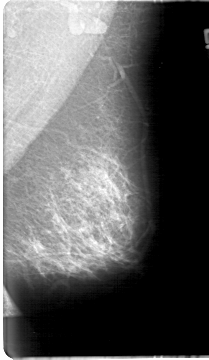

D_4067_1.RIGHT_CC

FILE: D_4067_1.RIGHT_CC.OVERLAY

TOTAL_ABNORMALITIES 1

ABNORMALITY 1

LESION_TYPE MASS SHAPE OVAL MARGINS MICROLOBULATED

ASSESSMENT 0

SUBTLETY 4

PATHOLOGY BENIGN

TOTAL_OUTLINES 1

BOUNDARY